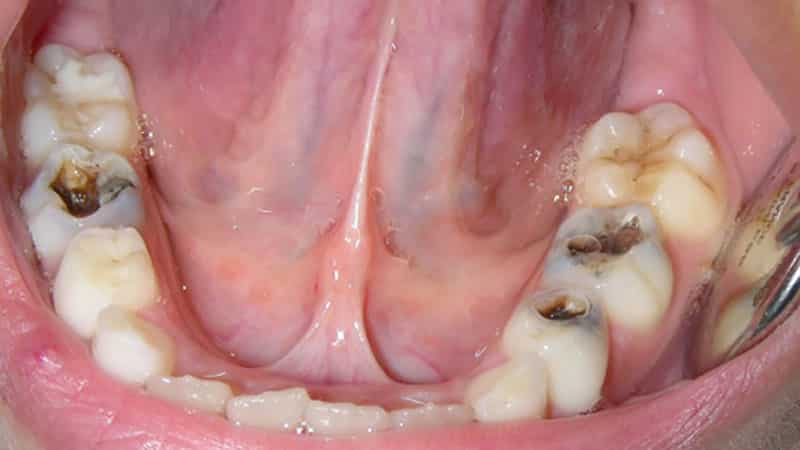

Пульпит молочных зубов у детей — распространенная проблема, требующая внимательного подхода и своевременного лечения. Молочные зубы, несмотря на временность, играют важную роль в формировании прикуса и развитии челюстно-лицевой области. В статье рассмотрим, как распознать пульпит, методы лечения, необходимость удаления нерва и возможные последствия для здоровья ребенка. Эта информация поможет родителям принять обоснованное решение и обеспечить ребенку необходимую стоматологическую помощь.

Задержка с обращением за медицинской помощью может привести не только к ухудшению состояния ребенка, но и к возникновению осложнений, таких как лимфаденит, периодонтит и периостит (так называемый «флюс»). Эти состояния представляют серьезную опасность как для здоровья, так и для жизни ребенка, поэтому обращение к врачу при первых симптомах воспаления в ротовой полости должно быть срочным. На фоне общей интоксикации и присоединения бактериальных осложнений последствия могут быть непредсказуемыми.